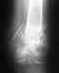

В предыдущем сообщении к сожалению не удалось прикрепипь все снимки.Сейчас это исправляю.Высылаю все снимки в хронологии.

Прошу Вас прокомментировать динамику. Почему пластина опустилась? И наблюдается ли все-таки сращение?